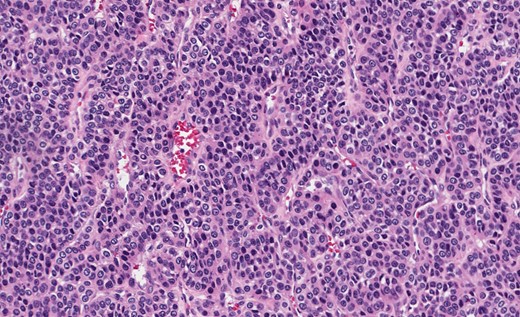

Gastric GT. Note the well-circumscribed submucosal lesion surrounding small vessels (H&E stain, ×20).

Grossly, GTs are multinodular, soft and rubbery on sectioning [3]. The cellular nodules are separated by streaks of gastric smooth muscle, which also surrounds the tumor [3]. Histologic features are central round to oval nuclei with inconspicuous nucleoli and clear to eosinophilic cytoplasm with distinct cell borders [1] (Figs. 3 and 4). GTs are positive for α-smooth muscle actin, vimentin, calponin and caldesmon. They are most often negative for CD117, CD34, chromogranin and synaptophysin [3, 6].